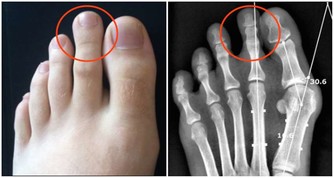

黃疸、肝臟腫大、肝區疼痛、脾大、腹水、下肢浮腫及肝功能異常,